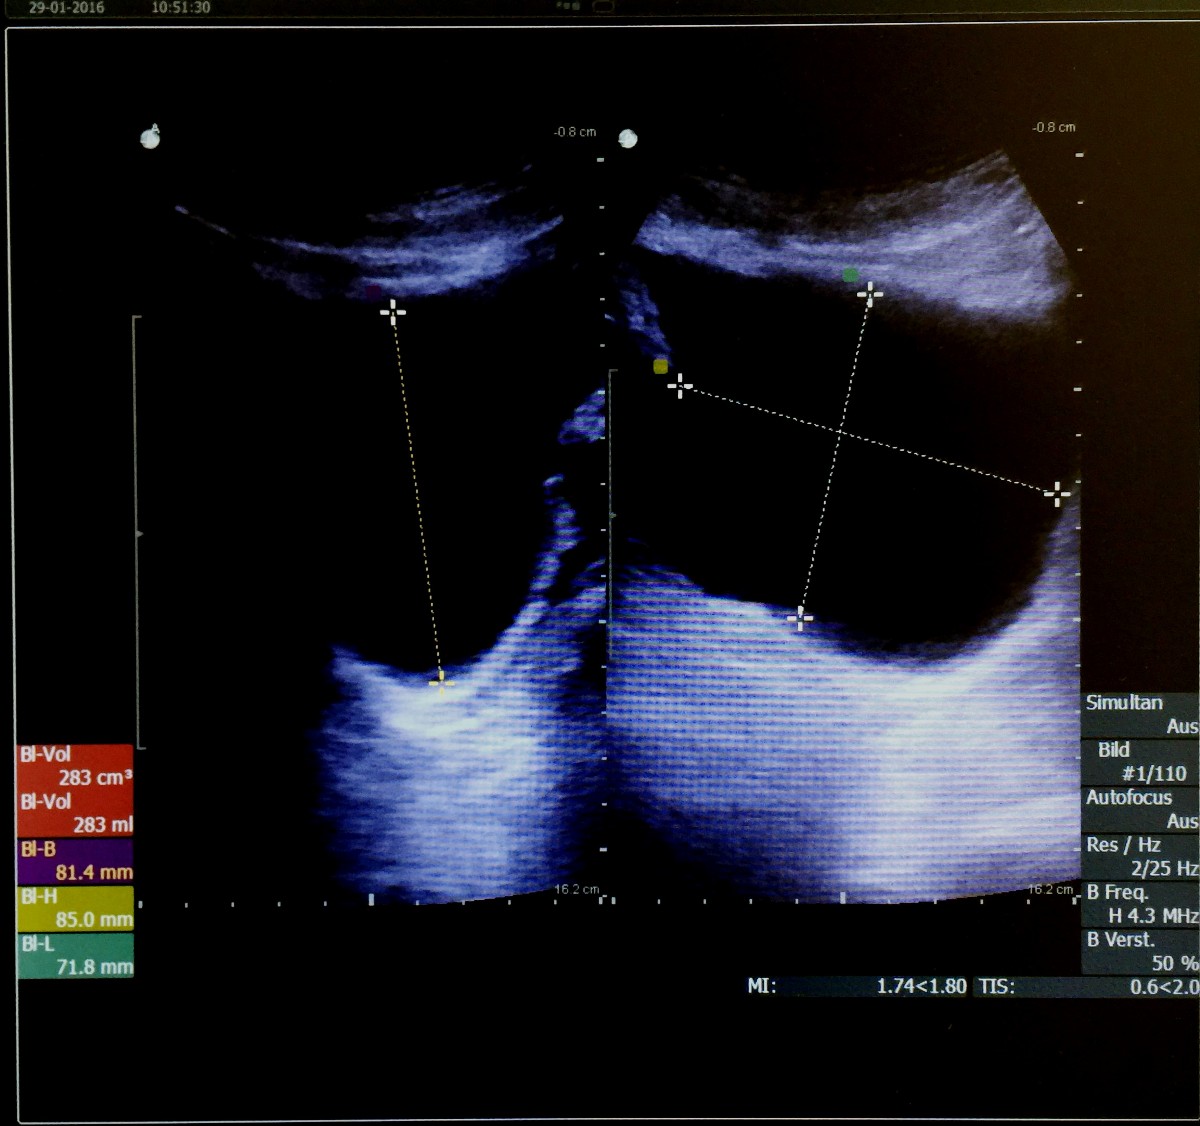

Mitralklappendegeneration Tierklinik Sattledt

Vorgestellt wurde uns „bob“, ein vierjähriger mopsrüde, der seit längerem unter leistungsschwäche litt. Angiostrongylus (a.) vasorum oder französischer herzwurm ist ein nematode, der im adulten stadium im rechten herzen und in der arteria pulmonalis von hunden parasitiert. Die gefässgrenzen wirken unscharf, die bronchien sind ebenfalls schwieriger erkennbar.

Eine röntgenuntersuchung beim hund ist ein etwas aufwendigeres verfahren als eine standarduntersuchung. Angiostrongylus (a.) vasorum oder französischer herzwurm ist ein nematode, der im adulten stadium im rechten herzen und in der arteria pulmonalis von hunden parasitiert. Lungenwürmer benötigen für ihre entwicklung einen sogenannten zwischenwirt.dies sind für den lungenwurm nacktschnecken und gehäuseschnecken, seltener aber auch frösche und andere.

Angiostrongylus (a.) vasorum oder französischer herzwurm ist ein nematode, der im adulten stadium im rechten herzen und in der arteria pulmonalis von hunden parasitiert. Damit das röntgenbild deutlich wird, darf das tier sich nicht bewegen. In vielen fällen ist es möglich, den.